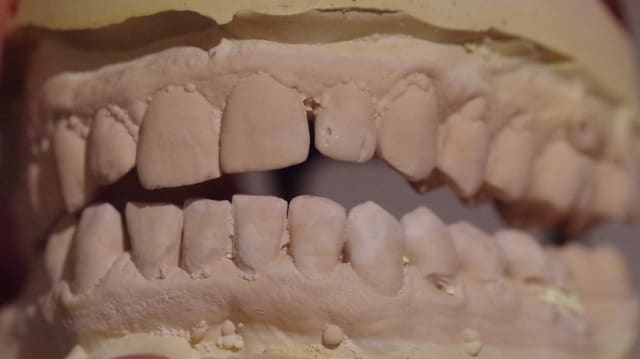

J’ai mis des photos des modèles qui n’arrivent pas bien sur à être en occlusion.

Le patient occluse uniquement côté droit au niveau prémolaire et molaire.

Je me suis amusé aussi à mettre en occlusion les modèles côté G ( comme on voit sur une photo) et bien évidemment le côté droit était en inocclusion.